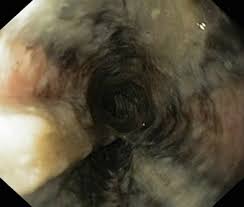

La necrosis esofágica aguda, conocida en la literatura médica como “esófago negro” o esofagitis necrotizante aguda, constituye una entidad clínica poco frecuente, caracterizada por un patrón endoscópico distintivo que llama la atención por su intensidad y claridad diagnóstica. Durante la esofagogastroduodenoscopia, se observa típicamente una mucosa esofágica distal que presenta una decoloración difusa, de tono negro profundo, circunferencial, que se detiene abruptamente en la unión gastroesofágica, delimitando de manera neta el territorio afectado. En algunos casos, esta afectación puede progresar de manera proximal, comprometiendo extensiones variables del esófago, pero siempre conservando su aspecto característico, lo que la diferencia de otras formas de esofagitis o lesiones mucosas.

El diagnóstico definitivo suele basarse en la esofagogastroduodenoscopia, donde se observa la clásica mucosa negra circunferencial del esófago distal. Esta visualización puede corroborarse mediante citología con cepillo o biopsia, confirmando la ausencia de epitelio escamoso viable, presencia de abundantes detritos necróticos y compromiso de la mucosa, que puede extenderse a la submucosa y, en casos graves, a la muscularis propia. La histología adicionalmente revela infiltrado leucocitario intenso, trombos vasculares, fibras musculares desorganizadas y cambios inflamatorios significativos, que reflejan la extensión de la necrosis y la respuesta tisular.

El diagnóstico diferencial incluye entidades que producen pigmentación oscura en la mucosa esofágica, como melanoma maligno, acantosis nigricans, depósito de polvo de carbón, pseudomelanosis y melanocitosis del esófago, por lo que la correlación endoscópica y histológica resulta crucial. La predilección casi universal por el esófago distal se atribuye a su menor vascularización relativa y a la exposición directa al contenido gástrico, que aumenta la vulnerabilidad a la necrosis isquémica y química.

- Etapa uno: esófago gravemente afectado, con mucosa negra circunferencial, friabilidad, exudados ocasionales amarillos, pérdida del reflejo a la luz, rigidez de la pared y distensión insuficiente de la luz.